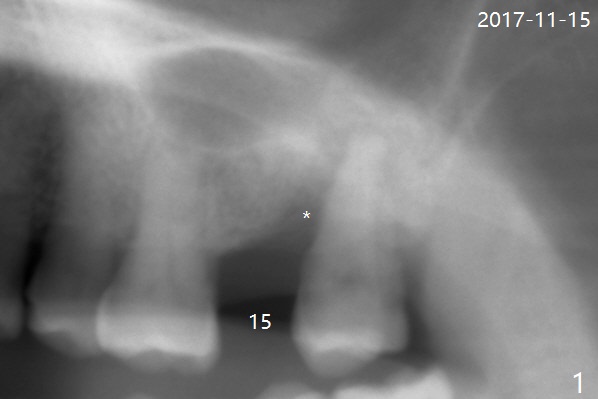

A 61-year-old woman requests #15 implant post ones at #2 and 6 because of pain in mastication (Fig.1). Examination shows that the tooth #16 has advanced periodontitis with mesial bone loss (Fig.1 *). It appears that there is insufficient bone for #15 implant. Bone graft seems necessary at #16 after extraction. There is severe hemorrhage post extraction. Osteogen plug is inserted for hemostasis prior to placement of allograft (Fig.2 *). The socket opening is covered with 12x12 mm Amnion-Chorion Membrane and 5-0 Polysyn. The socket seems to heal 9 days postop (Fig.3). The bone graft in the socket of #16 three months postop (Fig.4 *) will support an implant to be placed at #15 distal (Fig.5 *).